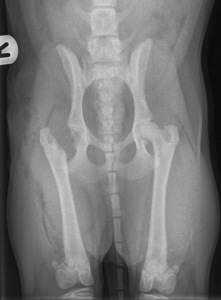

- Εκτομή κεφαλής και αυχένα του μηριαίου (FHNE) (Εικόνα 3):

- Εφαρμόζεται σε μικρόσωμες κυρίως φυλές και στόχο έχει την κατάργηση της άρθρωσης και επομένως και των συμπτωμάτων. Αποτελεί και την επέμβαση εκλογής για την αντιμετώπιση περιστατικών άσηπτης νέκρωσης της κεφαλής του μηριαίου οστού (Legg-Calve-Perthes disease).